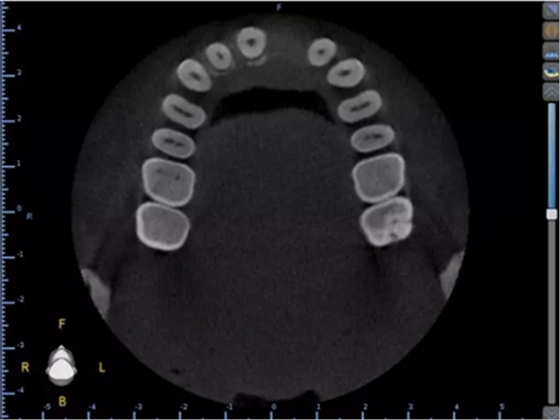

1.術(shù)前CT

2.術(shù)前植體設(shè)計(jì)

3.術(shù)前導(dǎo)板設(shè)計(jì)